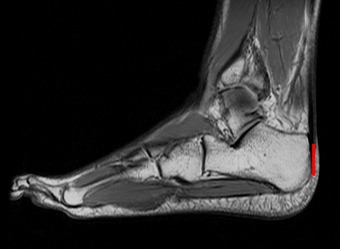

In their new investigation, Raichlen’s team calculated rates of oxygen consumption for eight experienced distance runners as they ran on a treadmill for 10 minutes at 16 kilometers per hour (10 miles per hour). On a separate day, an MRI scanner took images of each man’s heels and Achilles tendons.